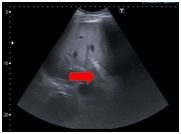

A 49-year-old male patient presents with a clinical picture of 11days of vomiting and diarrhea accompanied by abdominal pain, fever and jaundice during the last two days. Clinical history is positive for systemic hypertension, obesity and smoking. Physical exam showed tachycardia, jaundice and tenderness in the upper abdomen. Lab works showed: no leukocytosis, neutrophilia of 92%, liver enzymes of 115mU/ml and 179 mU/ml. Alkaline phosphatase of 129U/I, total bilirubin levels of 5.2mg/dl, Direct bilirubin of 3.3mg/dl, indirect bilirubin of 1.9 mg/dl, HDL of 250U/l, Amylase of 289U/dl, Lipase of 1900U/L, C-reactive protein of 24mg/dl, Electrolytes, renal function and coagulation were all normal. Hepatobiliary ultrasound showed a collapsed gallbladder (Figure 1). Bile system MRI showed thickened gallbladder wall, no gallstones, normal bile duct, dilated superior mesenteric vein with flow defect suggesting thrombosis (Figure 2). Contrast abdominal CT showed peri-appendicular inflammatory changes including a single fluid collection of 17x16mm, peripancreatic fluid and SMV flow defect-opacification indicating thrombosis (Figure 3). Normal Endoscopic ultrasound (Figure 4). The patient had findings suggesting systemic inflammatory response syndrome however in the absence of peritoneal irritation and ongoing pancreatitis, a conservative antibiotic treatment was chosen with ampicillin tazobactam, anticoagulation therapy with LMW heparin for 10days. The patient is discharged with a 21day antibiotic and 6month anticoagulation therapy. Appendectomy was programmed thereafter and the patient had full recovery.

Figure 2 Fatty liver, Gallbladder with dilated wall without gallstones, no bile duct dilation nor stones. Inflammatory peripancreatic fat changes due to pancreatitis. No peripancreatic collections, increased SMV diameter with flow defect indicating thrombosis.